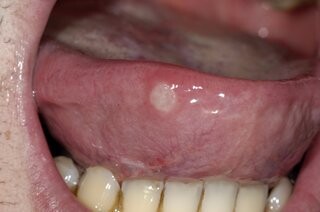

A white spot on the tongue surrounded by a red, inflamed halo is probably an apthous ulcer, more commonly referred to as a canker sore. Aphthous ulcers is a painful inflammatory condition that occurs in the oral soft tissue and on the tongue - often as one or more oval/round or well-defined, grey-yellow ulcerations surrounded by redness..

These common and recurring lesions can be small or large and appear on their own or in groups. Canker sores are often painful, and scraping doesn't remove them.